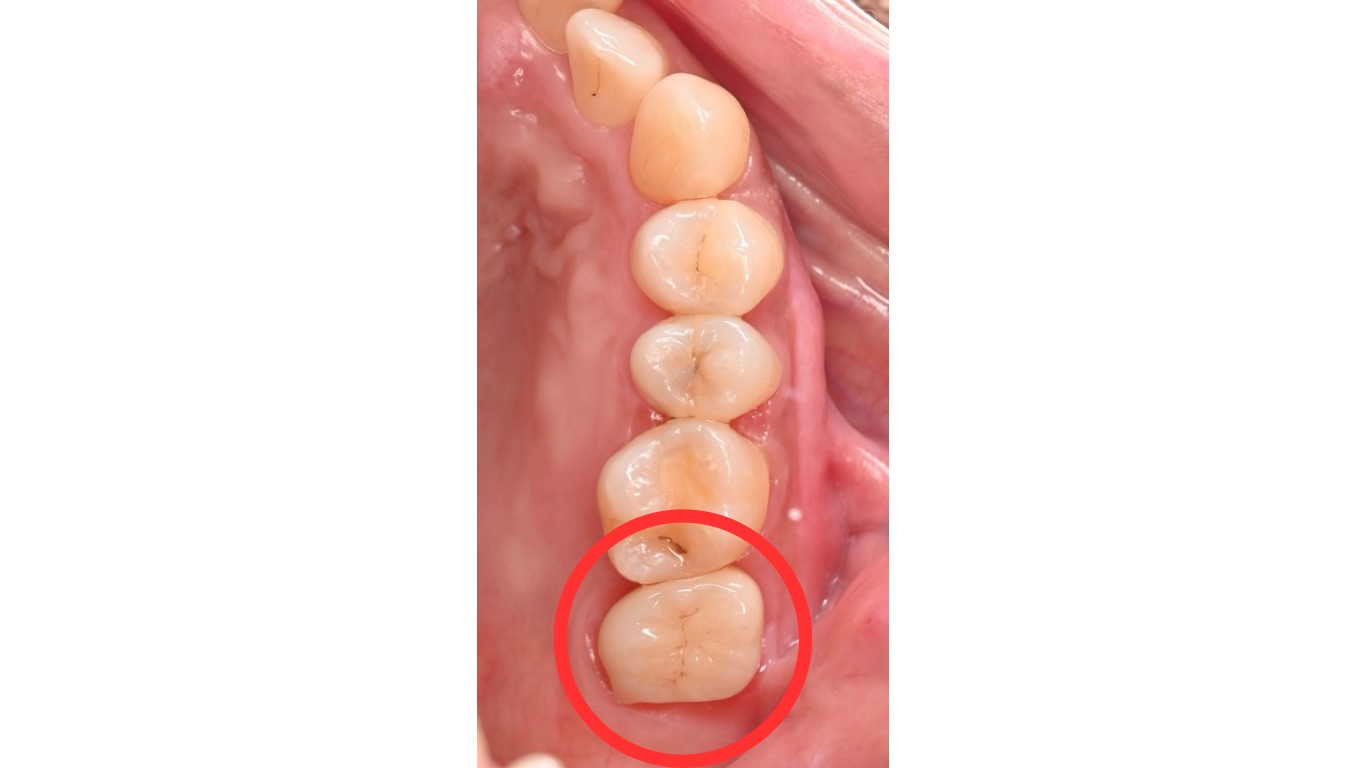

検査・診断

患部のCTを撮影したところ、根尖部(根の先端)に膿が貯まっていることを確認しました。

画像上では、根の先端にある黒く抜けている部分が根尖です。

この状態を根尖性歯周炎(Per)といいます。